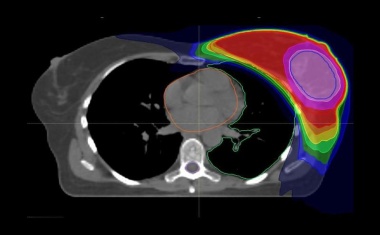

Das Universitätsklinikum Jena setzt auf innovative Strahlentherapie. Brachytherapie eröffnet neue Behandlungsperspektiven bei Leberkrebs.